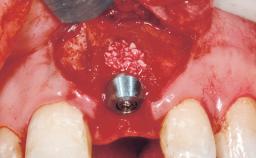

Placement Protocol | Early or late implant placement |

Bone Volume | Deficient horizontally, requiring prior grafting |